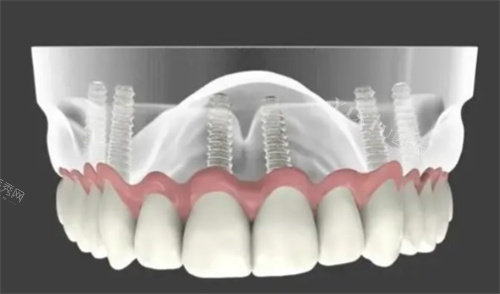

星海分院是新乡益美口腔的旗舰店,位于河南省新乡市红旗区人民路星海20号楼126商铺(人民东路南)。该分院在规模、设备、医生实力和种植牙技术等方面都具有明显优势。星海分院拥有经验充足的种植牙医生团队,能够开展高难度的种植牙项目,如穿颧穿翼种植、全口即刻负重种植等。此外,星海分院还引进了智能化X光系统、激光治疗仪器等新型口腔医疗设备,确保诊疗的明确性和安心性。

三、高难度种植牙项目

新乡益美口腔在种植牙领域具有显著的优势,尤其是在高难度种植牙项目上表现突出。医院的种植牙医生团队经验充足,能够根据患者的口腔状况和需求,制定个性化的治疗方案。例如,刘亦然医生擅长牙齿美学修复、中老年复杂义齿、全口种植牙修复等;周小涛医生则擅长复杂牙齿种植、ALL-ON-4种植以及无牙颌即刻种植、穿颧种植等。

此外,益美口腔星海分院还提出了“种植体长期确保,种植牙8年确保,长期维护”的服务约定,这不仅体现了医院对种植牙质量的信心,也给患者带来了更多的确保和安心。